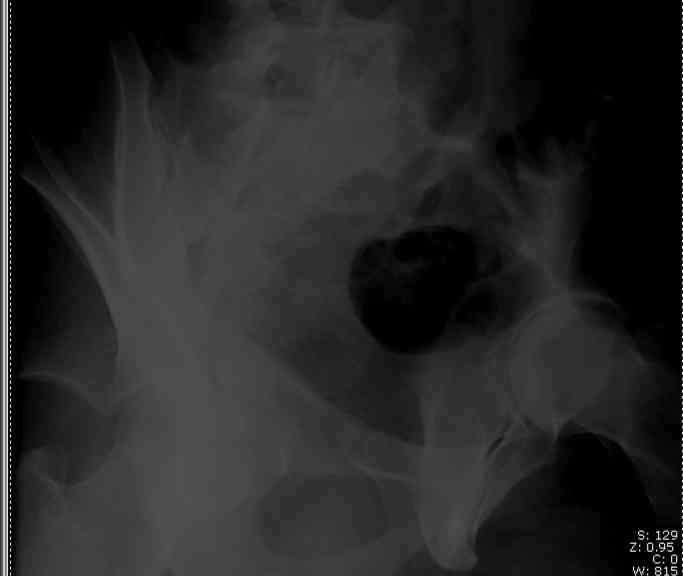

I'll include a few images of a similar injury in a similarly large male patient. This patient "showed up" in our ER c/o hip pain 2 months after being treated in the lateral position, without a quality reduction, without an anterior column transverse supporting implant, with an unbalanced plate applied too medially, with insufficient caudal segment fixation...it took over 8 hours and a 3+ l blood loss to debride the callus from front then

back, excise the HO, release his sciatic nerve, reduce the head-transverse-wall, and fix it...and now it's a staging procedure.

I have another patient 23 years of age, post wall + transverse frx, had surgery 10 months ago elsewere in Ankara without reduction and still has

pain and limp. Hip is posteriorly dislocated and head is destructed by the plates and

screws.

Any suggestion other then arthrodesis or artroplasty?